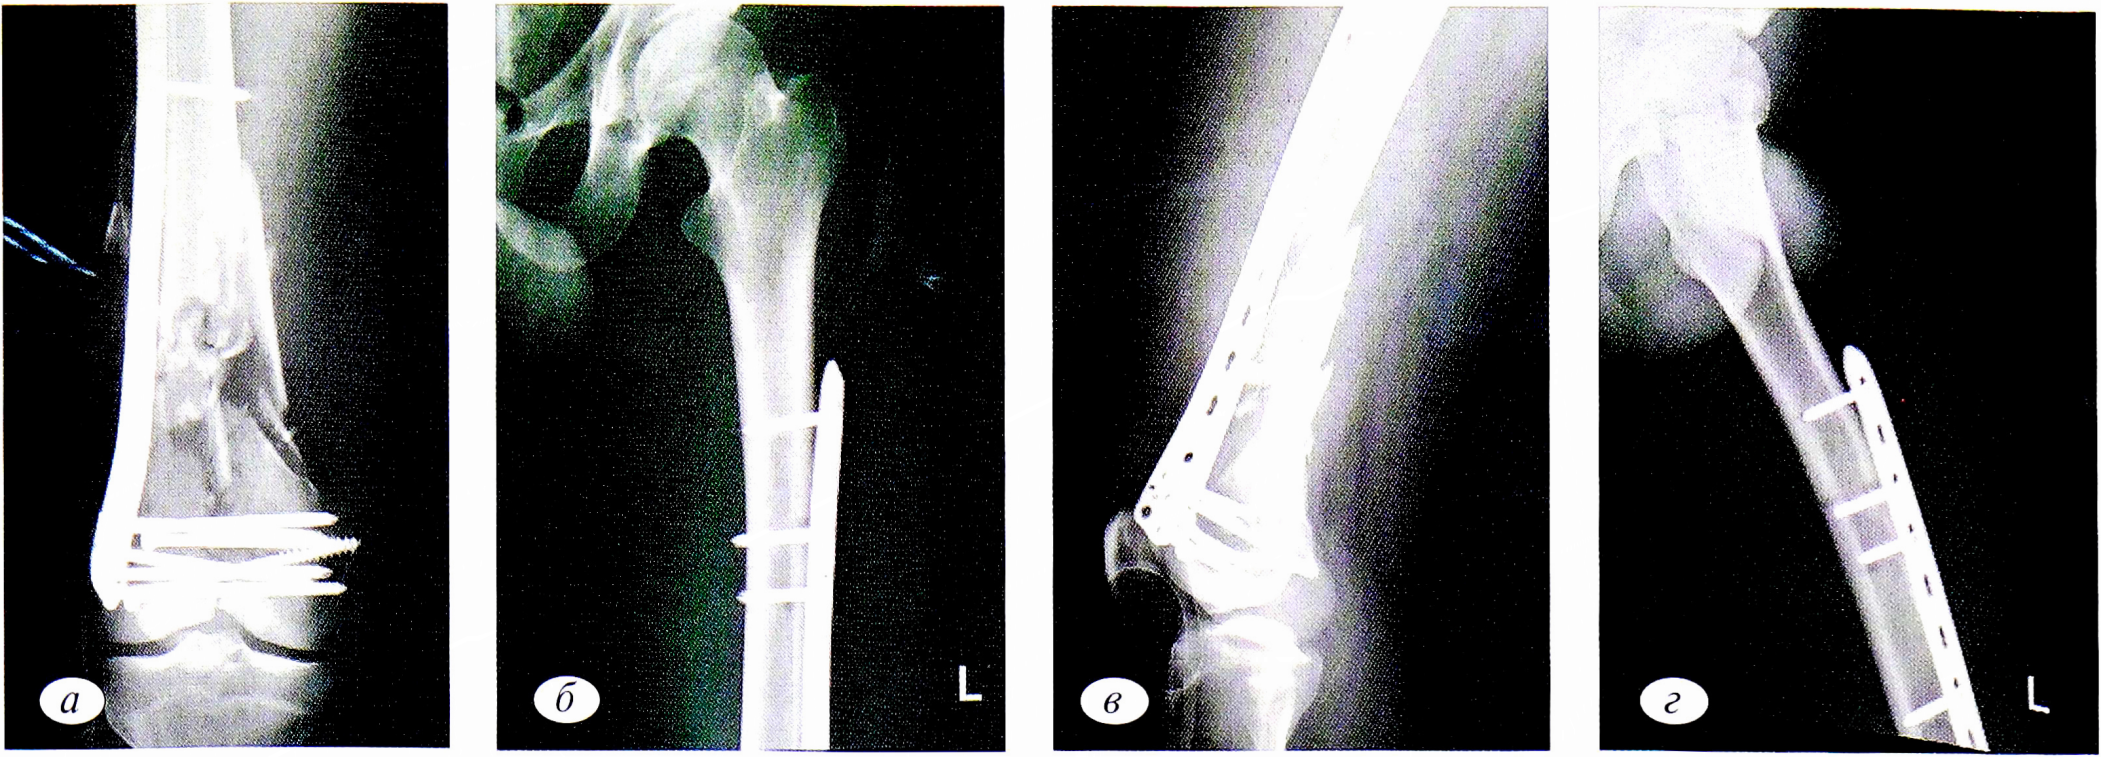

На 5-е сутки после спадения отека выполнен второй этап последовательного остеосинтеза: демонтаж аппарата внешней фиксации и накостный остеосинтез пластиной с винтами (рис. 3).

Рис. 3 (a, б, в, г). Пациент М. Рентгенограммы после накостного остеосинтеза пластинами и винтами.

Fig. 3 (a, b,с,d). The patient М. X-rays after plate osteosynthesis plates and screws.